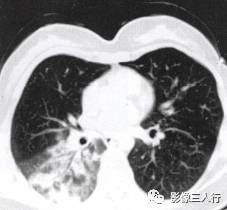

胸部影像常呈肺段或肺叶急性炎性实变。影像实变期表现为密度均匀的致密影,在实变 区中可见空气支气管征。其病理基础是由于广泛的肺泡腔内炎性渗出,肺充气明显减少,使 正常充气的各级支气管与实变的肺泡构成鲜明的对比,形成支气管充气征。见图4至图6。 医学百科网 | YxBaike.Com